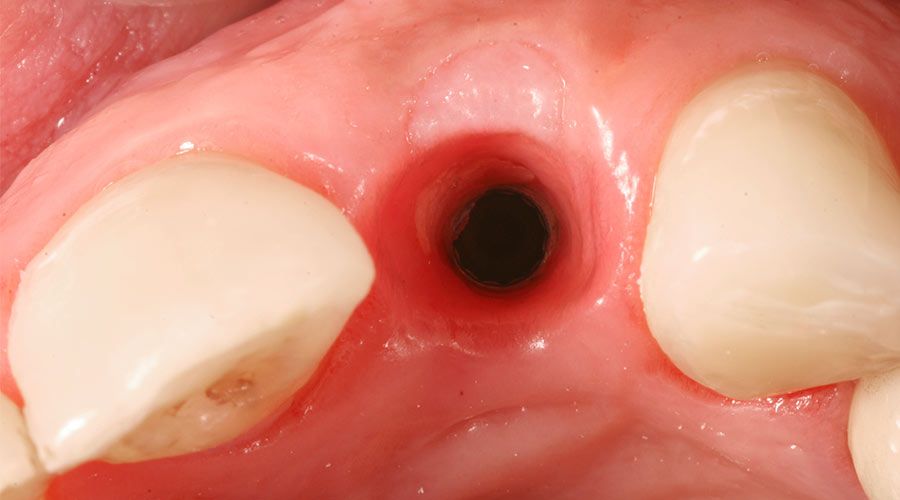

Several techniques and types of grafts can be used during the socket preservation procedure. To begin, a dentist or specialist will administer local anesthesia. When the procedure is performed in conjunction with an extraction, the area will already be numbed. Once the socket is exposed and cleaned, a membrane will be inserted to isolate the treatment area. This will prevent surrounding tissue from adhering to the site and generating new gum tissue. The barrier also prevents bacteria from spreading to the area, which could cause infection. The membrane may be derived from animal sources, which is then used to make collagen, or it may be made of a synthetic material.

Following placement of the membrane, the dentist will insert a bone graft into the socket. There are many graft types, including:

Lastly, the graft is covered either directly by existing gum tissue, or with a resorbable membrane or protective material. Then the area is sutured closed.